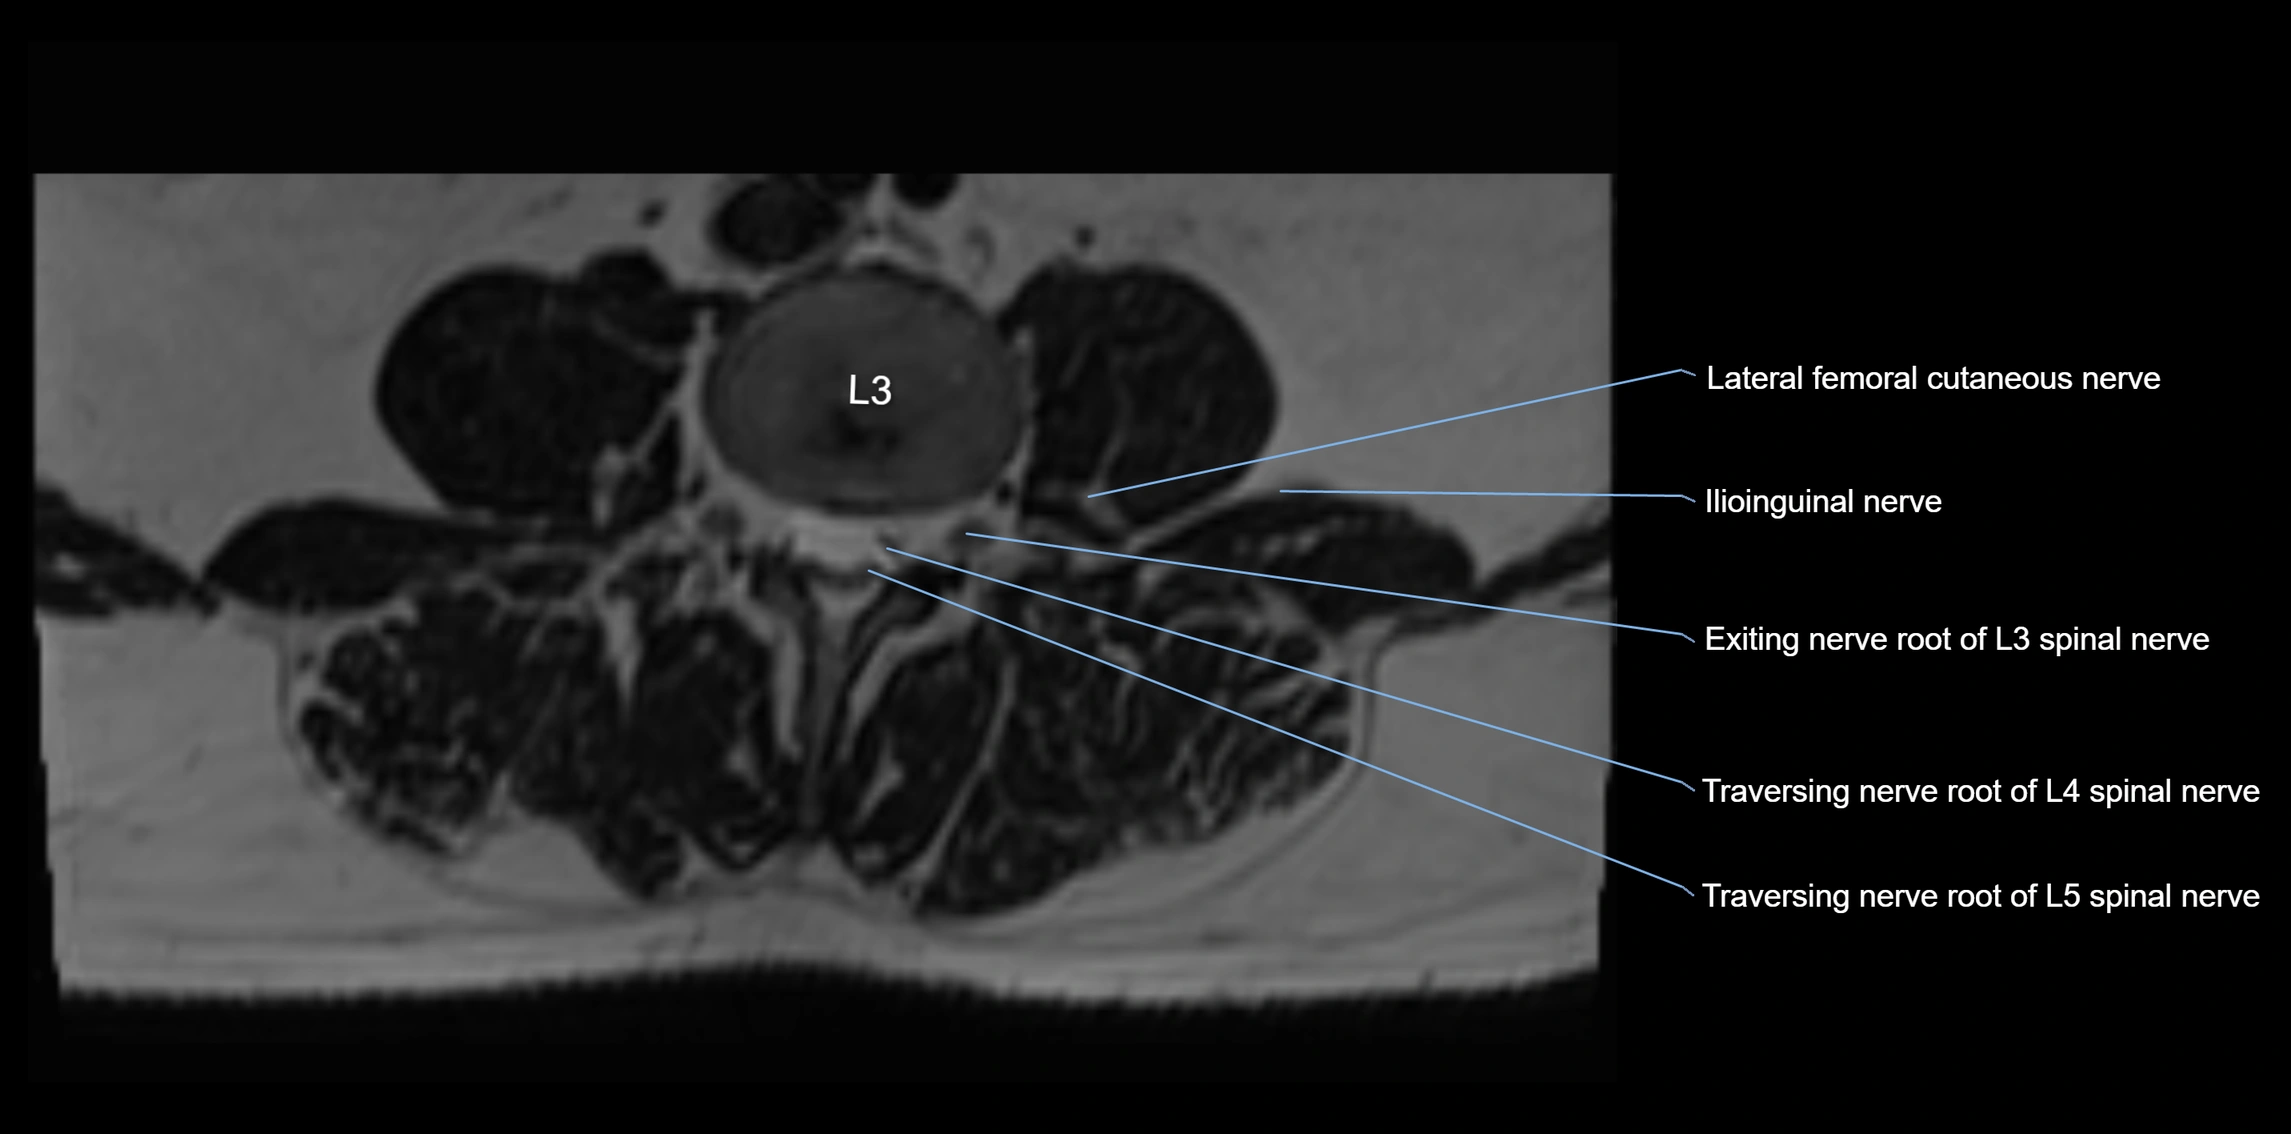

MRI image

image